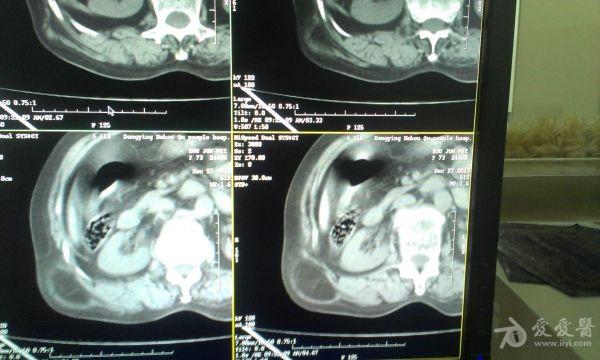

挺经典的腰疝

右腰部包块,随呼吸可运动。

非常经典的ct片,不知是继发于何种原因还是先天性的?里面内容物一般是肠管,很少发生较窄、嵌顿。